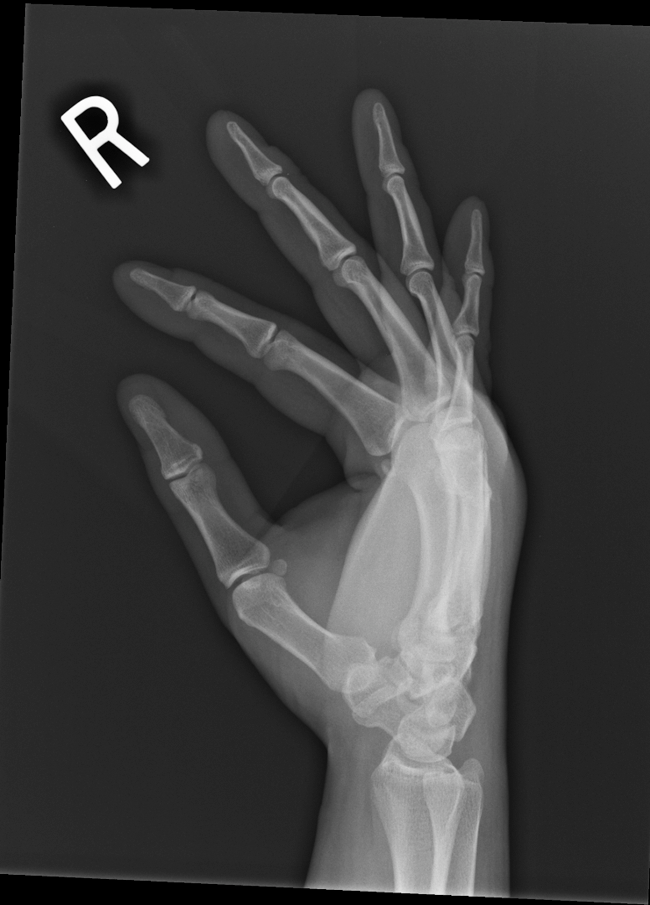

Boxer's Fracture